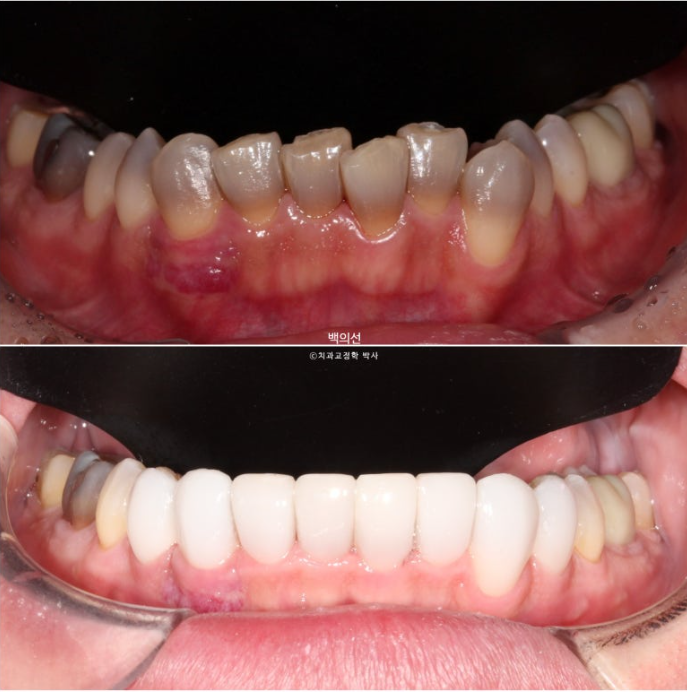

No-prep laminate has to be made thin, so the original tooth color inevitably shows through to some extent. In the facial photo, it can be seen that the original dark gray tooth color is showing through.

The way to prevent this gray tone from showing through is to remove some tooth structure and make the laminate thicker.

However, the patient wanted a no-prep approach, so we decided to accept some degree of gray tone.

I hope this post is helpful for those considering treatment for tetracycline-stained teeth.